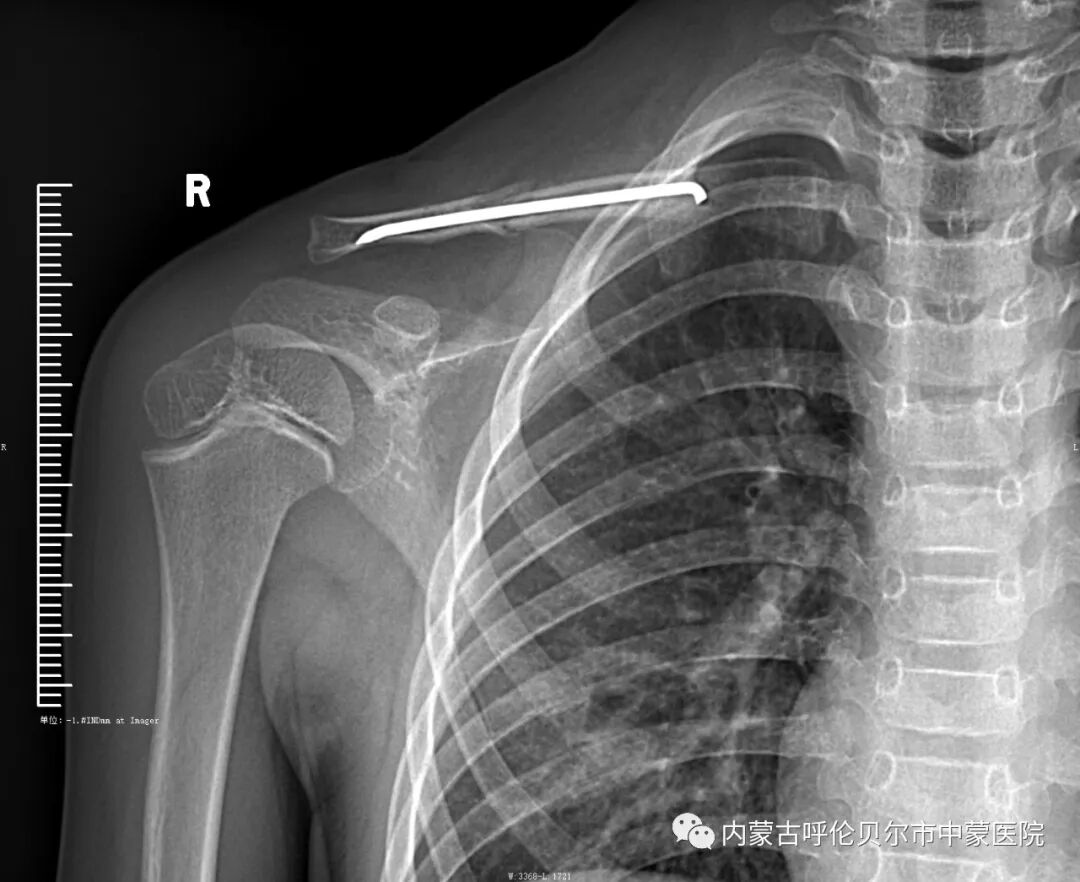

儿童2,来我院就诊前十二天摔伤,当时右侧肩部着地致右侧肩部疼痛、肿胀、活动受限,在当地行手法复位后静养,症状未见好转,遂来我院就诊,以"右侧锁骨骨折"收住院。